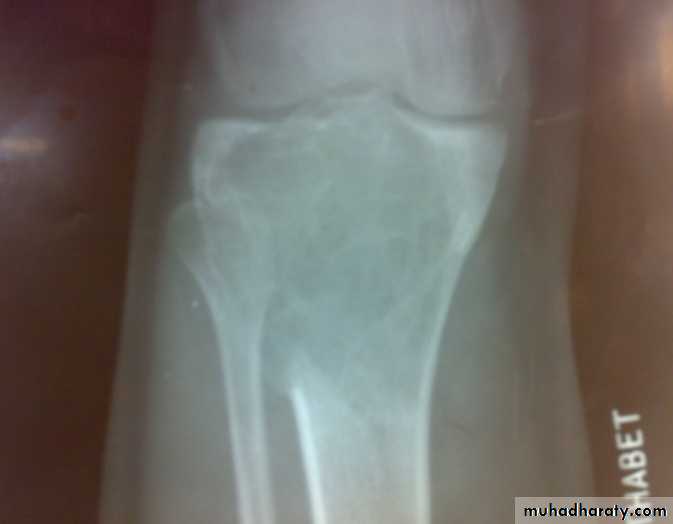

Patient presented by local pain and swelling or pathological fractures. Common site is the distal femur, proximal tibia, distal radius.

X-ray show eccentric osteolytic lesion in the end of long bone ,subchondral, trabeculated (soap bubble appearance). The cortex is thin, expanded or even perforated.